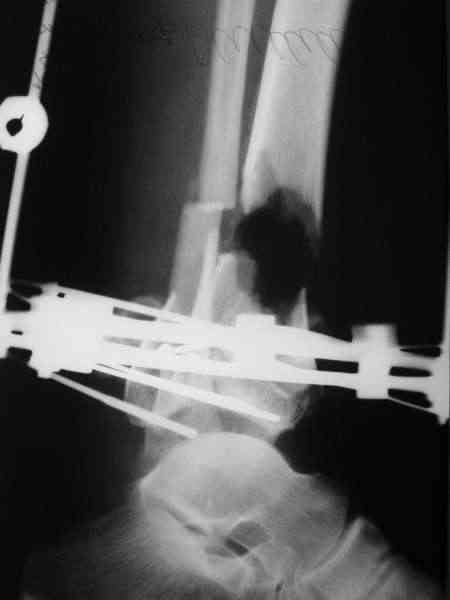

Re: Открытый вн.суставной перелом голени

Состояние раны: постепенно очищается, заполняется грануляциями с участками фибрина. Воспаление мягких тканей вокруг раны купировано. В глубине раны, ближе к дистальному отломку, остается небольшой "гнилой угол" с весьма скудным отделяемым. Две "большие" перевязки в течение недели, с частичными некр- и секвестрэктомиями в условиях операционной.

При закрытой попытке поймать и собрать отломки дистального фрагмента спицами с напайками, удача покинула меня.:-(

Срепонировать суставную поверхность мне не удалось. Только зря прошил ткани, а отломки остались в прежней позиции. Так и подмывало провести спицу через ахилл ... или пойти открыто задним доступом и притянуть винтом. Но смущает один момент: на чем будет держаться резьбовая часть винта, если передная поверхность разбита в хлам? Винт будеть елозить и не даст должной копрессии. Есть ли резон, при нынешнем состоянии раны, пойти на открытую репозицию заднего отдела суставной поверхности?